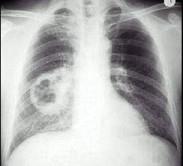

问题 男,54岁,咳嗽,伴胸痛两周,午后有低热,出汗较以前增多,胸片如图,最可能的诊断是()

选项 A.肺脓肿 B.结核空洞 C.韦格氏肉芽肿 D.肺癌 E.肺大泡

答案 D